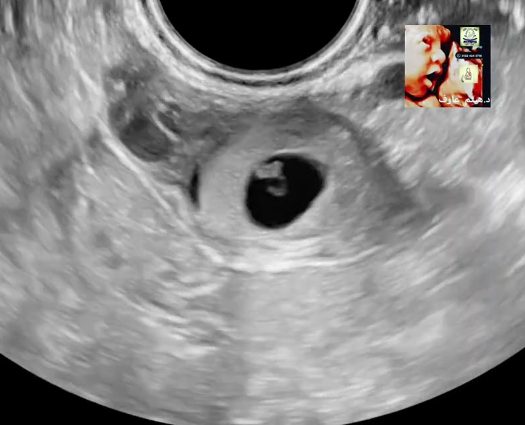

What is the bagel sign?

Ectopic pregnancy

What hcg represents an ectopic pregnancy?

A rise of less than 63% after 48 hours may indicate an ectopic pregnancy. When this happens the patient needs close monitoring and review.